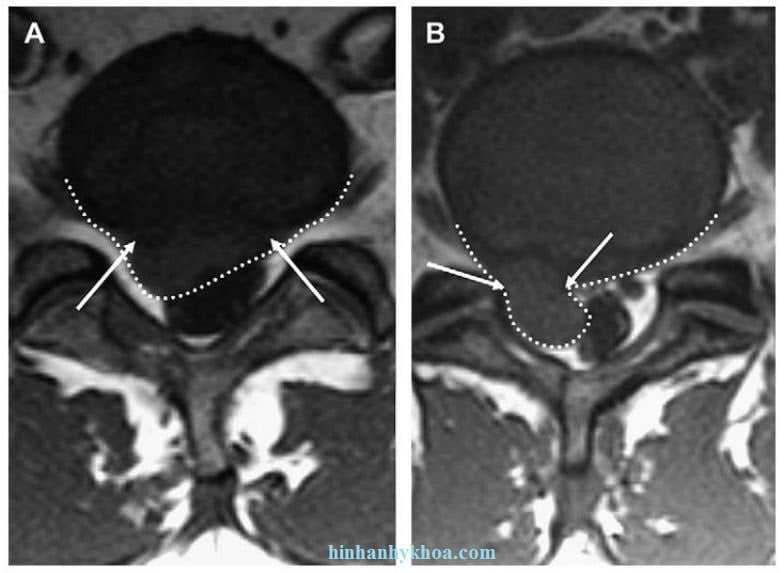

Ngược với protrusion, thoát vị đĩa đệm là extrusion nếu khoảng cách lớn nhất giữa các bờ của chất bị thoát vị lớn hơn các bờ của đáy thoát vị khi đo trên cùng một mặt phẳng. Ví dụ, nếu chất bị thoát vị vượt qua giới hạn của bờ trên hoặc bờ dưới đĩa đệm hay bề mặt thân sống thấy trên mặt phẳng sagittal thì đây là extrusion đĩa đệm (Hình 5). Nếu chất đĩa đệm bị extrusion có cổ hẹp và phần thoát vị rộng hơn khi thấy trên mặt phẳng axial thì đó cũng là một minh hoạ rõa nhất cho extrusion (Hình 6). Ngược lại, protrusion thì không thì vuợt qua bờ trên và bờ dưới đĩa đệm trên hình sagittal và có thể có cổ đáy rộng với phần protrusion của đĩa đệm không rộng như cổ của protrusion (xem Hình 5, Hình 6).

Hình 6. Hình axial T1W của cột sống thắt lưng ngang mức L4-5 cho thấy thoát vị đĩa đệm ra sau. (A) thoát vị (đường chấm trắng) thấy cổ rộng hơn (các mũi tên trắng); (B) thoát vị (đường chấm trắng) thấy cổ hẹp (các mũi tên trắng)